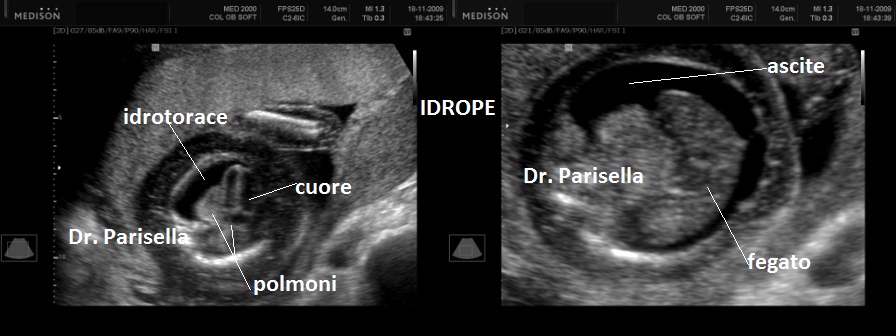

I segni ecografici sono:

• edema del sottocute: spessore > 5 mm.

• iperplacentosi: spessore placentare > 6 cm.

• polidramnios

• ascite

• effusione pericardica

• effusione pleurica

Come detto in precedenza l'accumulo di liquido deve interessare almeno due compartimenti.

Un primo orientamento sulle cause di idrope può essere fatto attraverso la localizzazione dell'accumulo di liquido: un accumulo generalizzato sin dal principio orienta verso una causa sistemica come l'anemia, mentre un accumulo inizialmente localizzato porta ad orientarsi verso una patologia locale ( es.: versamento pleurico >>>> Malformazione Adenomatoide Cistica Congenita del polmone).